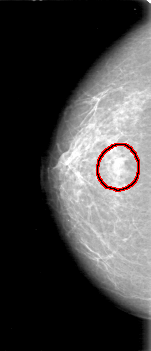

D_4027_1.RIGHT_MLO

FILE: D_4027_1.RIGHT_MLO.OVERLAY

TOTAL_ABNORMALITIES 1

ABNORMALITY 1

LESION_TYPE MASS SHAPE OVAL MARGINS OBSCURED

ASSESSMENT 0

SUBTLETY 3

PATHOLOGY BENIGN

TOTAL_OUTLINES 1

BOUNDARY